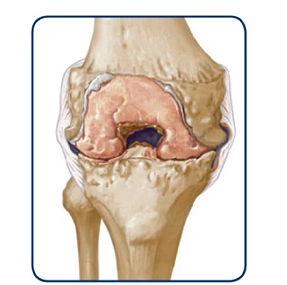

Joint bleeds—also called hemarthrosis—can happen when a joint is stressed. Repeated bleeds in the same joint may lead to chronic synovitis, where the joint lining becomes swollen and thick. Over time, this can limit movement and cause lasting joint damage.

Healthy knee

The bleed starts to enter the joint

The joint swells

If bleeds continue, it can degrade the cartilage and bone within the joint.

Over time, the joint may swell, change shape, and lose mobility.

Swelling of tissues in the knee may become permanent

Over time, this can lead to wearing away of the bone

Permanent damage results in a destroyed joint